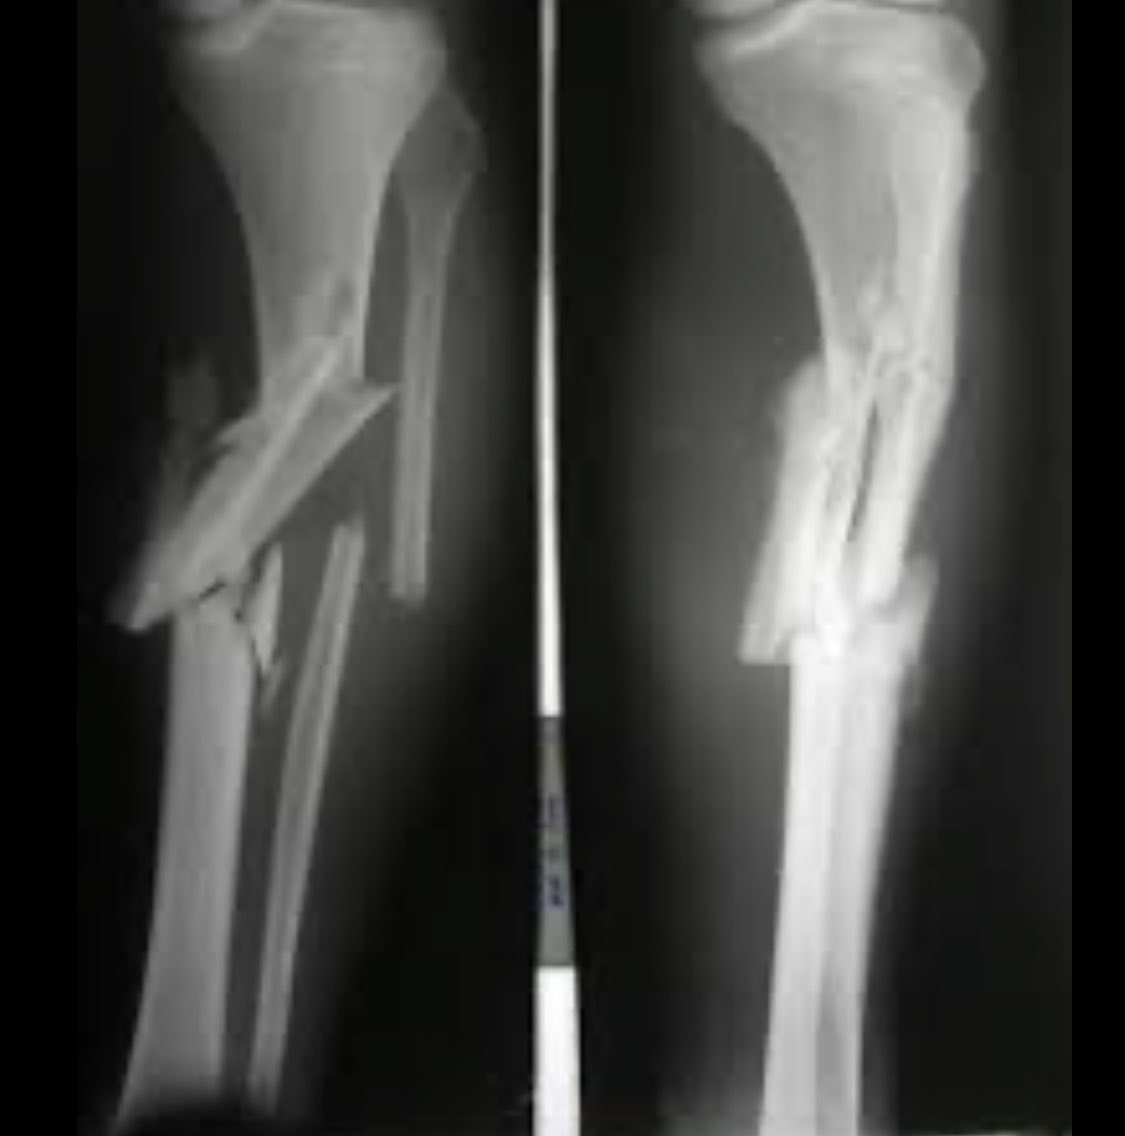

-طبيعة وخصائص الكسر

هذا يعني كشل الكسر ومكانه، هل الكسر قريب من المفصل او داخلة

هل الكسر في منطقة ميكانيكية لها خصائص مختلفة

لكن هناك انواع من الكسور كاالمعقدة والبسيطة

قد نلجأ احيانا لبعض المسميات او الوصف